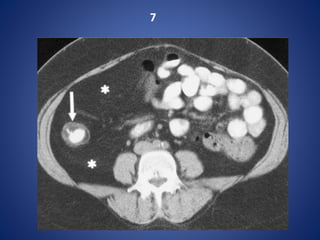

7

Crohn disease